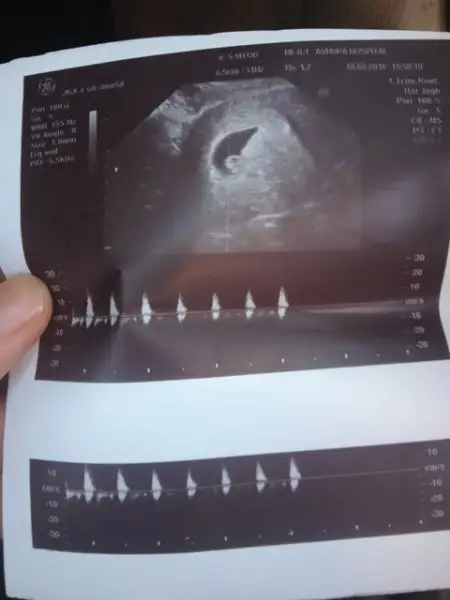

6 ya da7 haftalık usg varsa onu atarmısın ordan da bakayım bi. 8. haftada yer değiştirebiliyor çünkü.

Burda da kız gibi :)) kesenin içinde sağ tarafa daha yakın.. bu da karından usg değilmiBu da tam 7+1 teyzesi

evet karından usg valla bizimki sürpriz olacak :) kıza da benzeten var erkeğe de :) ortalarda bir yerde sanki. allah hayırlısını versin hepimize :)Burda da kız gibi :)) kesenin içinde sağ tarafa daha yakın.. bu da karından usg değilmi

Yok CNm 8+5karından usg ve 6-7 haftalık mı burada?